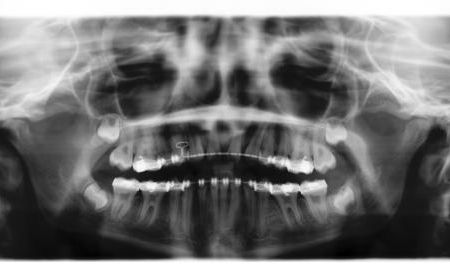

Röntgenbefund

Vor und nach der Behandlung

Die roten Punkte auf der linken Röntgenaufnahme markieren die Milchbackenzähne ohne Nachfolger, die ausgleichend enfernt wurden. Auf der rechten Aufnahme sieht man die Situation nach dem Lückenschluß.